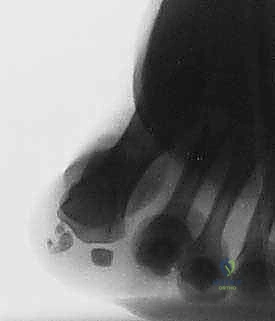

- Routine Radiographs: Obtain standing anteroposterior (AP), lateral, oblique, and axial sesamoid views. These views are often diagnostic for arthrosis, osteochondritis dissecans, or significant fragmentation.

Figure 4: A sesamoid view demonstrating significant fragmentation of the tibial sesamoid, indicative of chronic pathology.

Figure 4: Another sesamoid view highlighting fragmentation.

* Differentiating Bipartite Sesamoid from Fracture: This can be challenging. A fracture line is often sharp and irregular, while a bipartite sesamoid typically has smooth, well-corticated margins. AP radiographs taken in neutral and dorsiflexion can sometimes reveal separation of sesamoid segments in an unstable fracture.